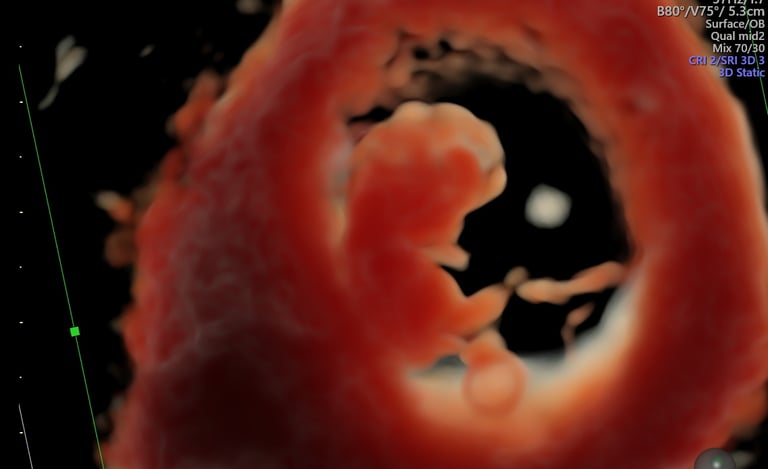

ecografía de viabilidad

4 - 11 semanas